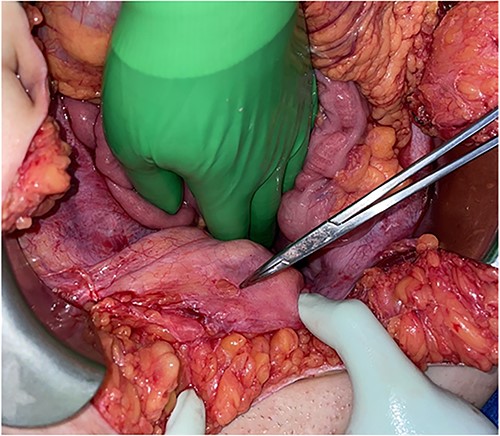

Computed tomography (CT) abdomen and pelvis demonstrated an air-filled tract from the pelvis to mid abdomen, suggestive of a foreign body in the anterior abdomen at the level of the umbilicus (Fig. 1). The radiology report for this CT scan suggested that this foreign body may be located within the urachal remnant.

CT scan of abdomen and pelvis showing the presence of an air-filled foreign body in coronal and axial view.